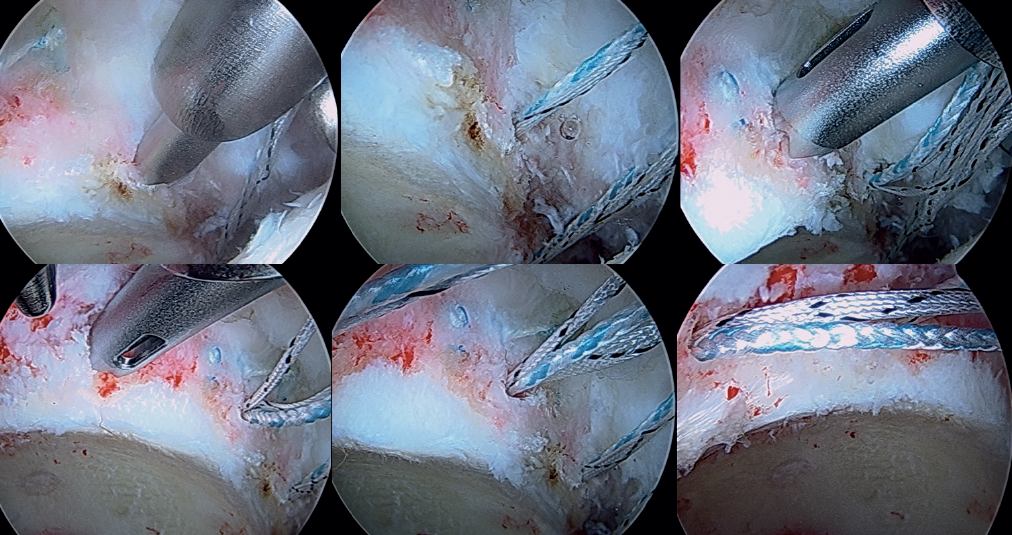

Pre-drilling and placement of acetabular anchorings

From the modified anterior portal, pre-drilling is performed at the 4 o'clock position (Figure 7) to implant an anchoring, with two possible variants: PressFT® 2.8 mm (Conmed), or an all-filament anchoring followed by threading of the extremity. Then, and also through the modified anterior portal or from the medial oblique portal, the first FiberTAK® Knotless 1.8 mm tensioning (Arthrex) anchoring is positioned 1 cm from the most anterior pre-drilling or anchoring, and its filaments are retrieved through the medial oblique portal. The successive FiberTAK® Knotless sutures are introduced through the medial oblique portal until reaching the posterior zone at the 8 o'clock position (Figures 8 and 9). During perforation and pre-drilling of the anchoring, the arthroscope is to be placed in a position allowing assessment of the joint cartilage, in order to make sure that the drill is not located between the subchondral bone and the surface of the joint cartilage. In order to prevent the anchorings from penetrating into the acetabular cartilage, the angle of the margin must be determined to ensure adequate placement. Lastly, the most posterior anchoring is introduced through the posterolateral portal and is also retrieved through the medial oblique portal. The successive filaments are placed in the field aligned and spread out in a fan-like manner from inferior-anterior to posterior-superior (Figures 10 and 11).